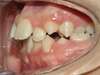

Cas 4 : Description

Chevauchement sévère. Traitement multibague sans extraction.

Avant

Après